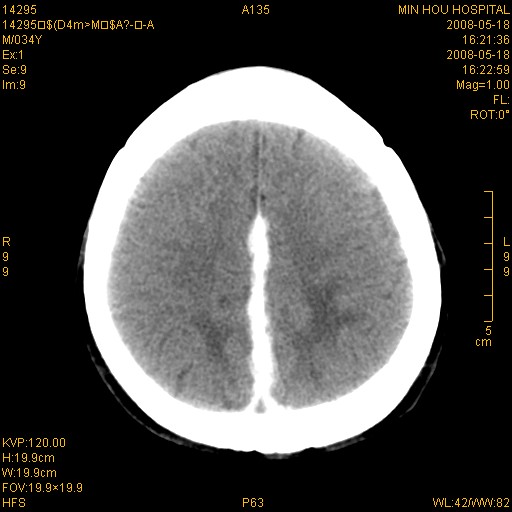

标题: CT13617:双顶叶白质水肿伴大脑镰小脑幕广泛钙化 [打印本页]

标题: CT13617:双顶叶白质水肿伴大脑镰小脑幕广泛钙化

多年前频发抽搐生活不能自理,行ct平扫,诊断为双顶叶占位。因贫未能进一步检查。

目前偶有抽搐,能从事油漆工作。原片未能获取。

双侧侧脑室后脚旁对称性低密度影,符合肾上腺白质营养不良(成人型)改变    小脑幕及大脑廉钙化  可考虑为生理性

支持:1、肾上腺白质营养不良.2、小脑幕、大脑镰广泛钙化。3、建议进一步检查。

硬脑膜钙化是主因,双侧顶叶白质密度减低是可能由于静脉路回流受阻所致。